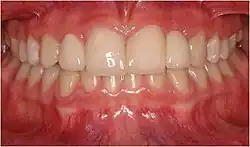

Unter einer Klebebrücke oder Adhäsivbrücke, auch Marylandbrücke, versteht man eine festsitzende Brücke als Zahnersatz, die mittels eines Befestigungskunststoffs an die säuregeätzte Schmelzoberfläche von Pfeilerzähnen geklebt wird und aus einem Metall- oder Keramikgerüst besteht.[1]

Weiter vorangetrieben wurde diese Methode durch neue Klebezemente und die Einführung neuerer mechano-chemischer Verbundsysteme, die den Kunststoff-Metall- bzw. Keramik-Metallverbund und damit auch die Langzeitprognose (Haltbarkeit) von Klebebrücken verbesserten. Zu Beginn der 1990er Jahre stellte Matthias Kern die zweiflügelige vollkeramische Adhäsivbrücke vor, in Hinblick auf Ästhetik und Biokompatibilität die bessere Alternative zur metallkeramischen Adhäsivbrücke.[10] Nachdem die zweiflügelige vollkeramische Adhäsivbrücke eine relativ hohe Frakturrate einer der beiden Verbinder zu den Nachbarzähnen aufwies, wurde sie von der einflügeligen vollkeramischen Adhäsivbrücke abgelöst, d. h. der fehlende Zahn wurde nur noch von einem Verbinder zum Nachbarzahn gehalten.[11][12]